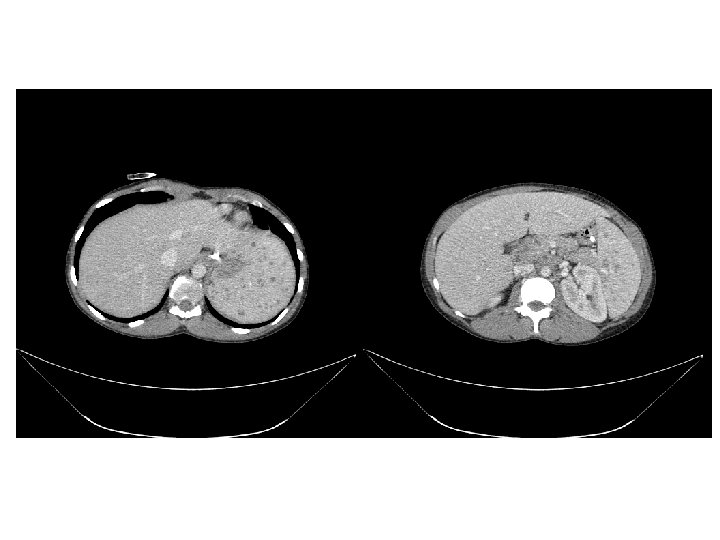

• Traitement de la tuberculose pulmonaire – Quadrithérapie débutée le 07 mai 2011 • Traitement de l’infection par le VIH – Truvada® Sustiva® le 19 mai 2011 (J 12) • Le 24 mai 2011 – Persistance de la fièvre (T=39 -41°C) – Scanner thoraco-abdomino-pelvien • Syndrome de masse ganglionnaire hilaire bilatéral sous carénaire, loge de Barety, latéro-trachéal et médiastinal • Foyer de condensation pulmonaire gauche • Transfert au CHU le 27 mai 2011